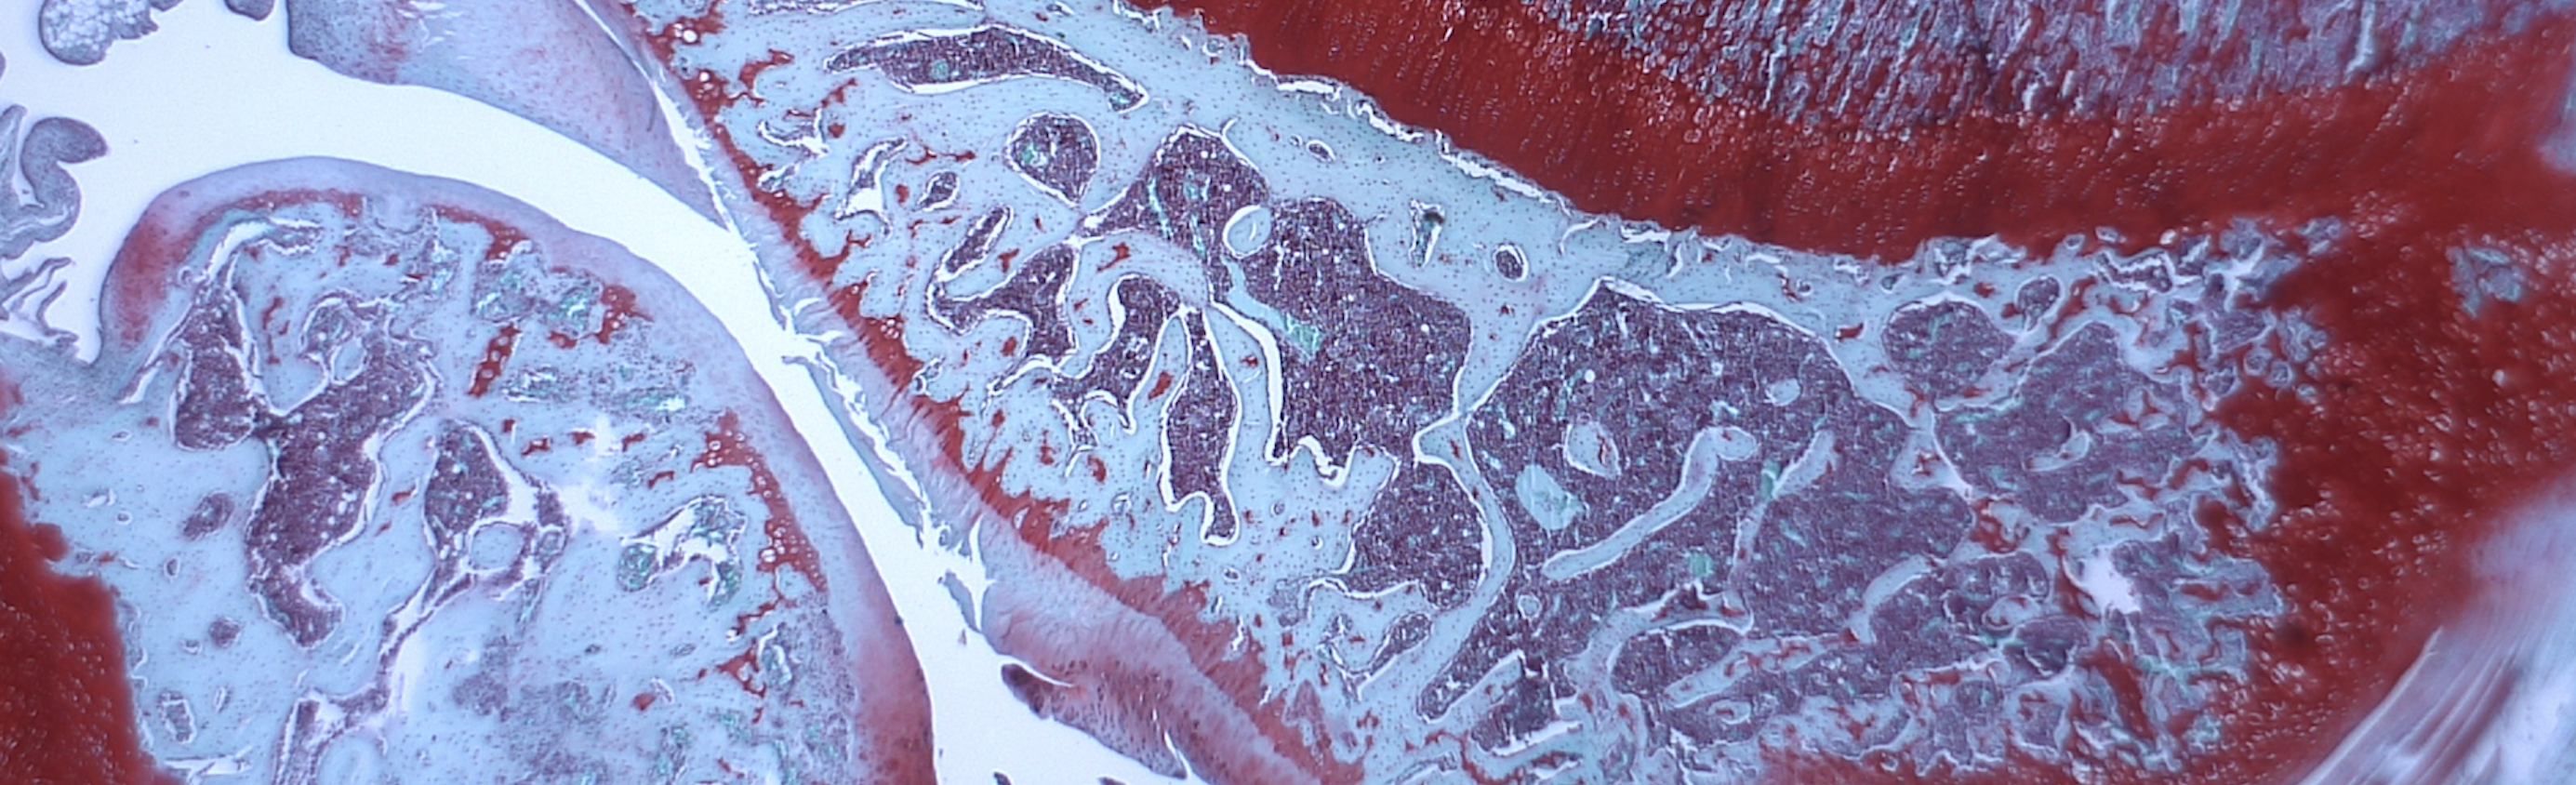

Tetrad offer a number of drug discovery solutions ranging from bespoke cell based assays, help with technical transfers, IB writing, consultancy, histology including immunohistochemistry and biomarker discovery. Indeed, Tetrad were instrumental in helping identify key pharmacodynamic (PD) biomarkers that Levicept currently utilise in our clinical programme. Tetrad developed assays with pg/ml sensitivities and moreover their understanding of the underlining biology has enabled a strong translational biological relationship for LEVI-04 across all studies conducted to date including patients. Indeed, these PD biomarkers are driving dose selection and enabling an understanding of mode of action in the clinic.

“It is a great pleasure to hand our histopathology processing over to such competent hands. Tetrad provides an extension of our capabilities and adds tremendous value to our preclinical research. The quality of their work is extremely high and delivery of results is timely. Communication with regards to project timelines is particularly excellent which facilitates the smooth running of projects from start to finish. I would not hesitate to recommend their services”.

“It has been my pleasure to work with the team at Tetrad on a number of histology and immunohistochemistry-based projects over the last few years. Often these studies required the delivery of high quality histology demonstrations to demanding deadlines – reflecting the needs of pathology data to inform decision making within clients research studies. Tetrad have performed this work superbly. On a number of occasions the team have developed protocols from first principles and I have been impressed by how they have worked protocol development and application activities into the agreed schedule without compromising on quality. Indeed, their commitment to quality control is impressive. I have enjoyed working with the Tetrad team and look forward to collaborating with them on future projects. I have no hesitation in recommending Tetrad for specialist histology and immunohistochemistry”.